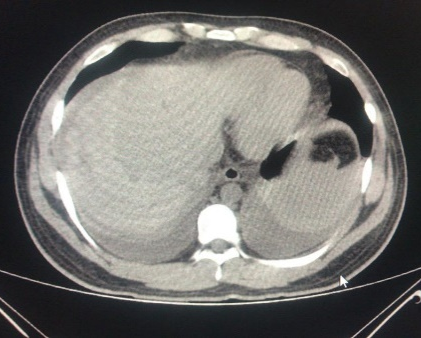

ERCP was performed successfully over 0.035-inch diameter guidewire, a Haraldsson type 3 duodenal papilla;3 Cholangiography showed a fill defect of 8mm, with a no bleeding, complete sphincterotomy, the common bile duct stone was extracted with balloon, without complication. Patient was followed for 6hours, and previous discharge, pain appeared at right upper quadrant. Colicky pain, diaphoresis, nausea and vomiting. We made new laboratory test, showing, and a drop of hemoglobine from 15g/dl previously to 10g/dl creating us the idea about patient was bleeding, maybe from the sphincterotomy, just giving no surgical management until then. Urgent computed tomography (CT) scan exhibited 13x11 cm subcapsular hepatic hematoma on the surface of the right hepatic lobe (Figures 1-4). He was treated with conservatory management with Tomographic control every 10days in 2 episodes, and every 2months, with hematoma regression until the month 6th.

Figure 4 96 hrs CT control. 50% Resorption.